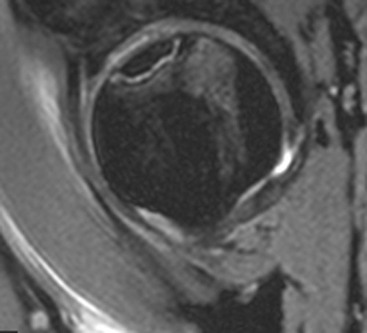

Avascular necrosis of the femoral head has many potential underlying causes (Table 46-1). MRI is the preferred technique, allowing early detection of signal change in the subchondral region of the femoral head. The ‘double line’ sign on fluid-sensitive sequences, characteristic of AVN, describes a low signal sclerotic line next to a high signal hypervascular line which demarcates the extent of the lesion (Fig. 46-41). There may be accompanying bone marrow oedema in the femoral head and neck. The extent of involvement on MRI has prognostic value in determining the outcome after decompressive surgery.27 Conventional radiographs are much less sensitive in the early stages of AVN, but as the process progresses they will typically show a linear subchondral lucency that progresses to articular collapse and sclerosis. Both hips should be imaged together, as bilateral involvement is common.